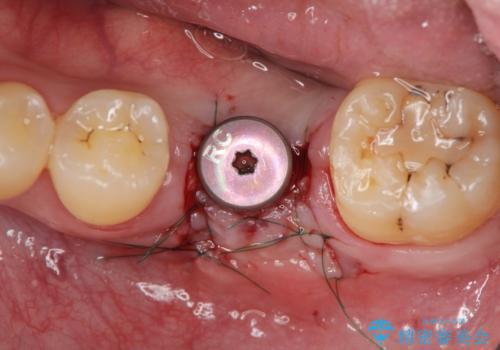

インプラントによる咬合機能回復

- 「長年虫歯放置した結果、抜歯となってしまった左下奥歯に歯を入れたい」、と希望され来院されました。

前後の歯は虫歯も治療歴もないため、前後の歯を削らなくてはいけないブリッジではなくインプラント治療による咬合機能回復を計画します。

- 46.2万円(仮歯・ストローマンインプラント・チタンカスタムアバットメント・ジルコニアクラウン)費用は治療当時の料金となります

減ってしまった顎骨に増骨処置を行うことで、より安定した環境で長く使用できるようなインプラント治療を行っています。